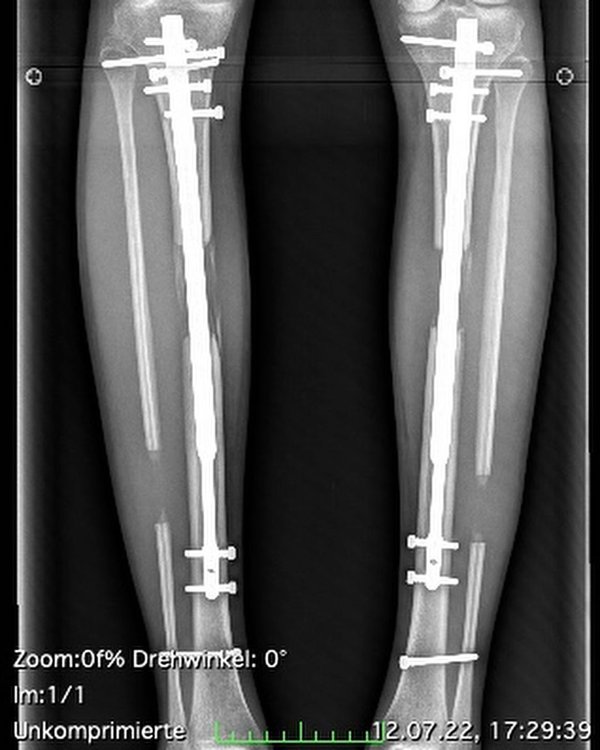

اعتبر كثيرون أن هذا الرقم لا يسمح لأن تكون هذه الفتاة عارضة أزياء مما جعلها تتعرض لمضايقاتٍ كثيرة أجبرتها على تمديد ساقيها بمقدار 8.5 سنتم ليصبح طولها حالياً 184 سنتيمترًا.

الجراحة كانت صعبة بالفعل واستمرت آثارها السلبية لمدة 8 سنوات إذ عانت من آلامٍ وإلتهاباتٍ حتى ان كثيرين تفاجؤوا من قبول الأطباء اجراء هذا النوع من الجراحات المخصص لإصلاح فرقٍ بين طول الساقين، بما معناه، أن الهدف يكون عادةً طبيًا.